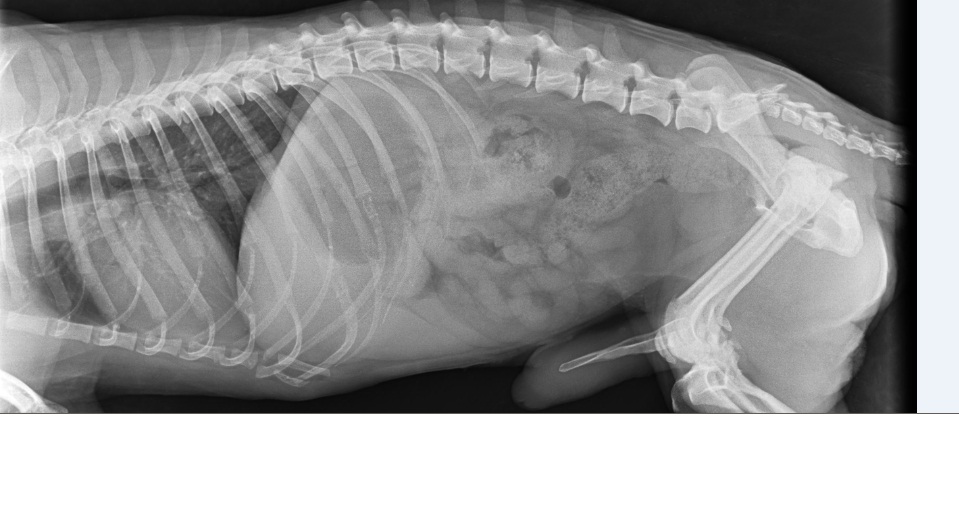

Ma to poprawić komfort życia bez bólu - i ruchomość kończyny - miednica jest tak popękana że niestety bez operacji nie będzie miał komfortowego życia. Postaram się wrzucić zdjęcia z RTG i opis konsultacji wczoraj już nie dałam rady. -

Kochani mamy dobre wieści, nawet bardzo dobre! Okazało się że tego pęknięcia kręgosłupa nie trzeba operować, doktor Bissenik obejrzał malucha, zrobił rtg ale zdjęcia wyszły bardzo kiepsko ponieważ kończynę miedniczną podwijał Tobi pod siebie - pewnie mu tak wygodniej było i mniej bolalo. Doktor znieczulił naszego chłopca i zrobiliśmy RTG w znieczuleniu - okazało się że ta miednica jest w bardzo kiepskim stanie a operacja powinna być wykonana do 3 dni po urazie a my dokładnie nie wiemy kiedy uraz nastąpił i napewno minęło sporo czasu od zdarzenia. Doktor powiedział że kość jest tak roztrzaskana i zgruchotana ( jest tam gruz ) że nie podejmie się w chwili obecnej operacji bo mógłby wyrządzić więcej szkody niż pożytku. Odłamki nie są na tyle duże aby mieć pewność że usunie się wszystkie. Aby zachować ruchomość stawu ( bo już w miednicy zaczęły się zrosty kości ) - jedyna możliwość to poczekać 4 tyg aż samo się troszkę podgoi i wykonamy zabieg resekcji główki kości udowej. Pozatym kręgosłupem mamy się nie przejmować bo zdarzyło się to w części bezrdzeniowej - Doktor powiedział że stan Tobiego nie jest zły - że będzie normalnie chodził po tej operacji. Narazie mamy zalecenie 4 tyg bezwzględnego klatkowania w kennelu tak aby ruch był ograniczony + dostaliśmy lek przeciwbólowy na 10 dni. Mamy się zgłosić za 4 tyg i umówić termin zabiegu. Korzystając z okazji że Tobi był w znieczuleniu poprosiłyśmy z Dorotą o podgolenie mu troszkę tyłka z sierści aby łatwiej było zachować higienę. On ma strasznie dużo kołtunów, zmechaconej sierści - jak wydobrzeje napewno trzeba będzie go podciąć aby piękna nowa sierść odrosła - ale to już w przyszłości :) Mamy też spory problem ponieważ miejsce w którym Tobi teraz przebywa - jest tymczasowe. Nie może tam długo zostać i tu pojawia się pytanie i zarazem prośba czy ktoś znalazłby kawałek kąta w domu aby Tobiego do i po operacji " przetrzymać " w klatce kennelowej ? Zapewniamy oczywiście karmę i usługi weterynaryjne - szukamy ciepłego, sprawdzonego miejsca. On jest totalnie bezproblemowy jeśli chodzi o " obsługę " - grzeczny, spokojny i cichutki jakby go nie było. Cudny pies, w gabinecie dał ze sobą zrobić wszystko, dosłownie wszystko... Prosimy pomyślcie, popytajcie...może ktoś się zgodzi zaopiekować Tobim I teraz ta mniej przyjemna rzecz - finanse... Za konsultację zapłaciłyśmy dzisiaj 237 zł Szacowany koszt operacji to 900-1000zł Za chwilkę wkleję zdjęcia i filmiki jakie nagrywała Dorota :) Bardzo bardzo bardzo jej dziękuję za dziś :******* i za obecność i wsparcie bo byłyśmy mega zestresowane -